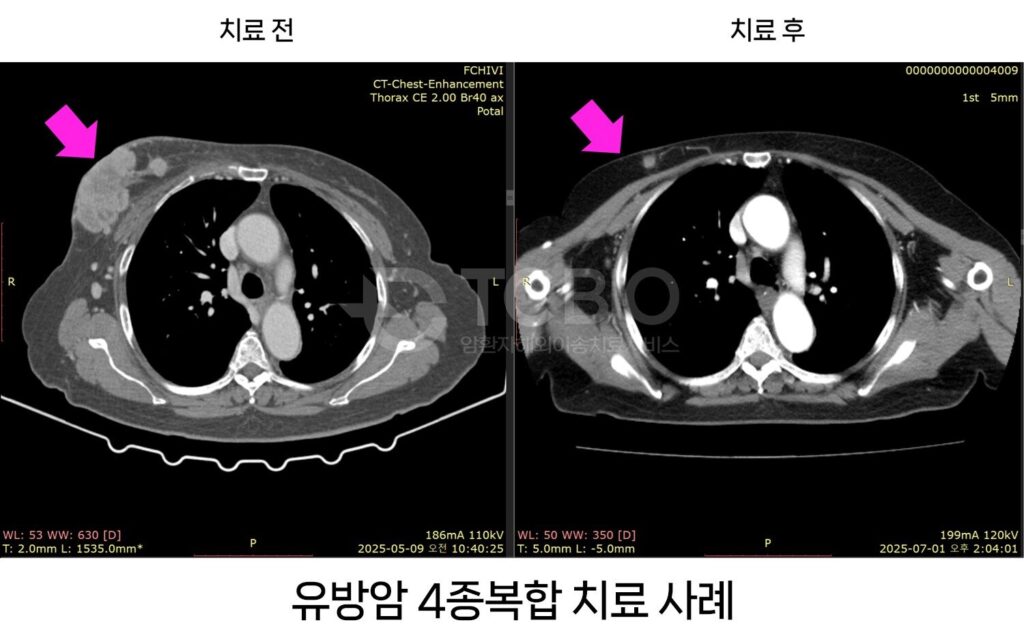

[한국일보] 4종 복합•해외 이송치료로 말기암 정복 나서

티시바이오(대표 이상우)가 말기 암에서도 치료 가능성을 보이는 4종 복합치료로 암 정복에 나서고 있다….

[월간암] 중입자치료를 못하는 말기암 환자, 더욱 강력해진 4종복합치료

중입자치료는 부작용을 최소화하는 비 수술적인 치료로 주목받고 있다. 그러나 중입자치료는 모두가 치료 대상이 되는 것은 아니다. 전이가 되었거나 혈관에 붙어 있는 경우, 두경부암에서 선양낭포암은 치료 대상이 되지만 편평상피세포암은 불가능하다. 췌장암 또한 췌장 머리 또는 (십이지장 천공위험) 혈관에 붙어 있거나, 전이가…

중입자치료가 불가능한 환자, IVR 등 4종복합치료로 해결

구효정(cancerline@daum.net) 기자입력 2025년 11월 14일 08:48분 중입자치료는 모두 대상이 되는 것은 아니다. 전이가 되었거나 혈관에 붙어 있는 경우와 두경부암에서 선양낭포암은 치료 대상이 되지만 편평상피세포암은 불가능하다. 췌장암 또한 췌장 머리 또는 (십이지장 천공위험) 혈관에 붙어 있거나, 전이가 된 경우 불가능하다. 이렇듯…